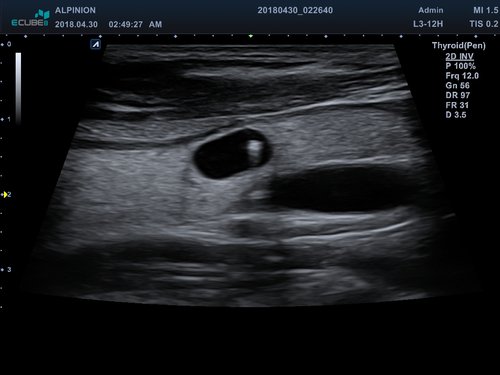

• Kleine Organe

• Endokavitär-Sonden

• EV3-10T (3-10 MHz) für Ultraschalluntersuchungen in Bereichen Geburtshilfe, Gynäkologie, fetales Echo, Urologie

• EC3-10T (3-10 MHz) für Ultraschalluntersuchungen in Bereichen Geburtshilfe, Gynäkologie, fetales Echo, Urologie